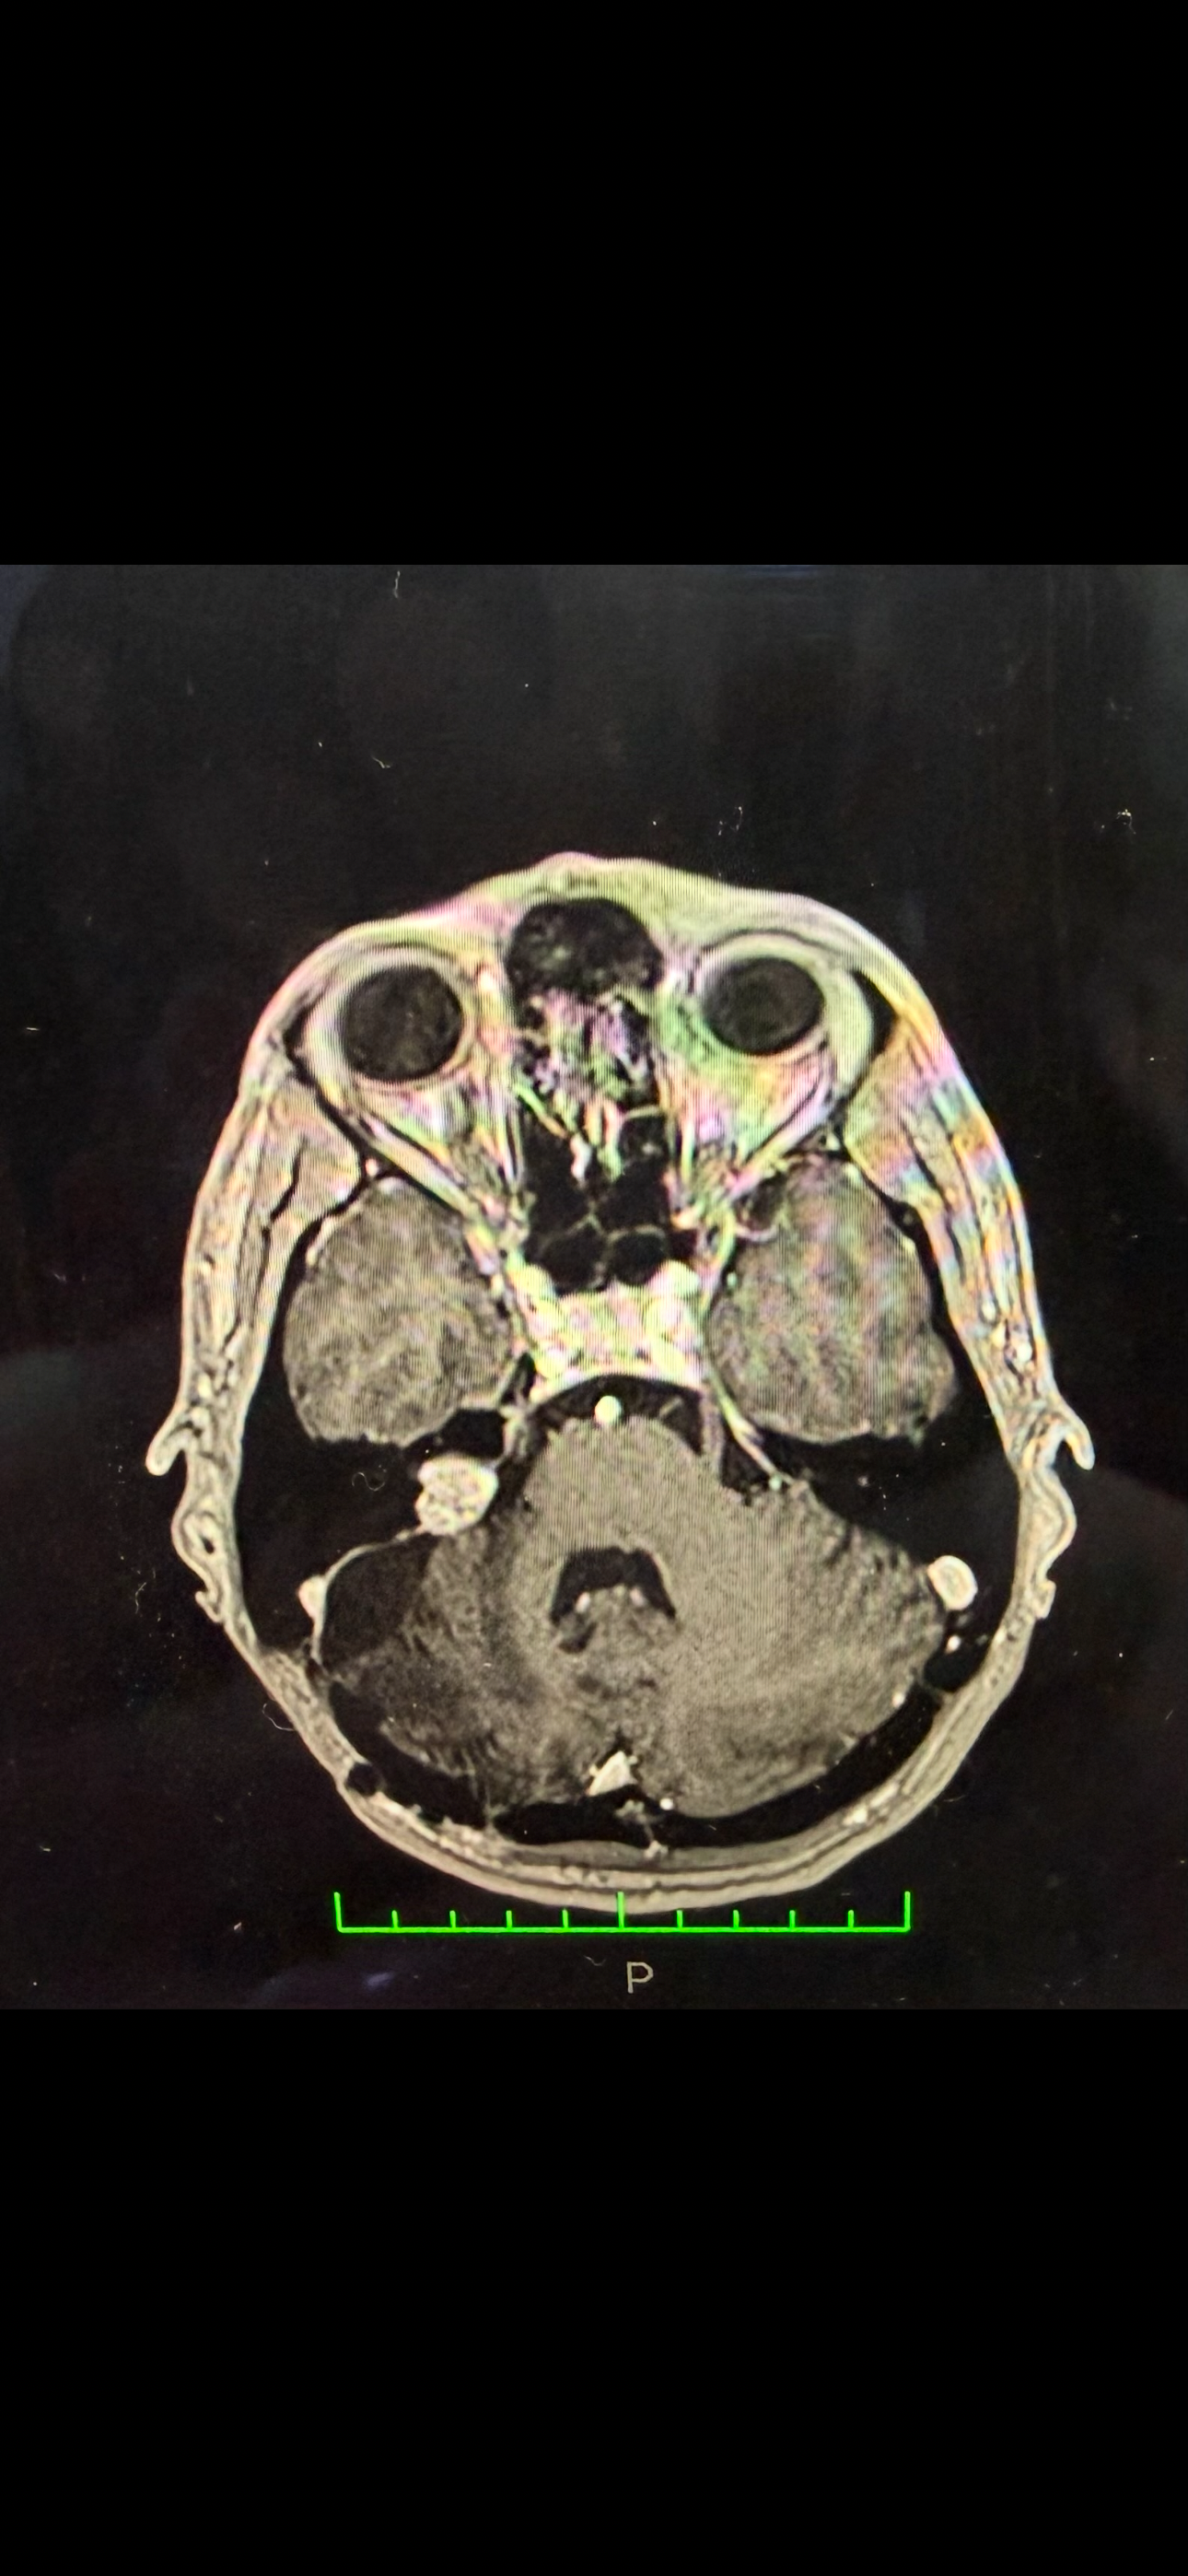

Në vitin 2017 u diagnostikova me një tumor në tru në anën e djathtë (acoustic neuroma). Në të njëjtin vit iu nënshtrova operacionit të parë në tru për heqjen e tumorit. Gjatë operacionit u dëmtua nervi facial dhe kjo më shkaktoi paralizë në anën e djathtë të fytyrës.

Në vitin 2025, rezonanca magnetike tregoi një tumor të mbetur me përmasa 14×12×10 mm.

Në janar 2026, tumori është rritur në 19×18×15 mm, që do të thotë një rritje rreth 5 mm vetëm brenda një viti.

Sot kam humbur plotësisht dëgjimin në veshin e djathtë dhe tumori vazhdon të rritet.